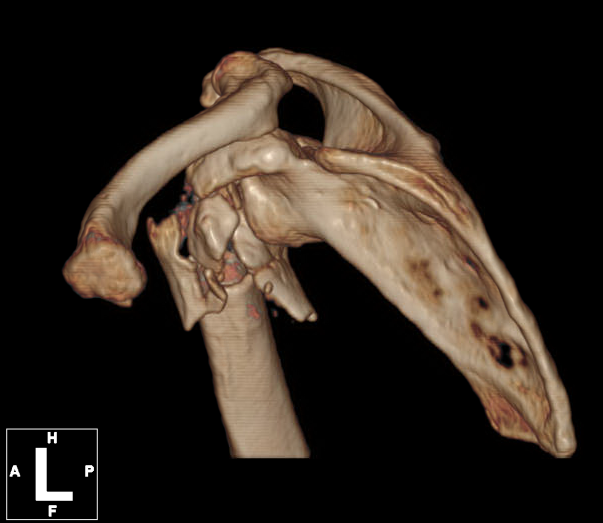

术前肱骨头CT

1、右肱骨近端骨折(Neer 4部分)